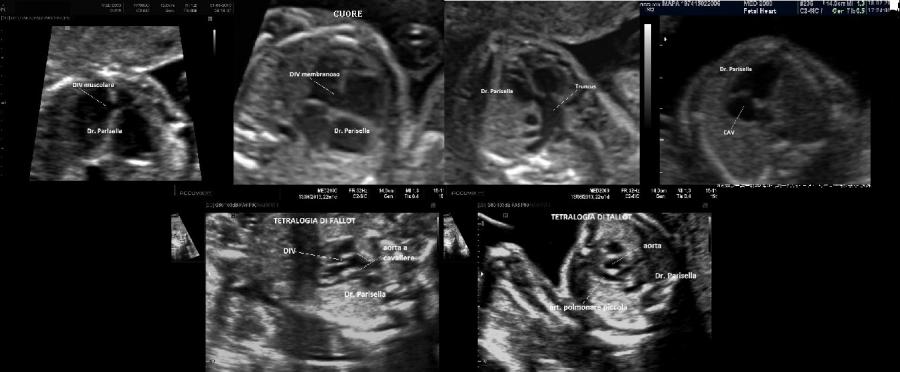

- il tipo I caratterizzata da placentomegalia ad aspetto multicistico, normosviluppo fetale e set cromosomico aggiunto di origine paterna (la dispermia è la causa più frequente di triploidia), micrognazia, anomalie del SNC (idrocefalia), cardiopatie, igroma cistico, oligoamnios.

- il tipo II caratterizzata da una placenta piccola, IUGR, set cromosomico aggiunto di origine materna (diginia), micrognazia, anomalie del SNC (idrocefalia), cardiopatie, igroma cistico, oligoamnios.